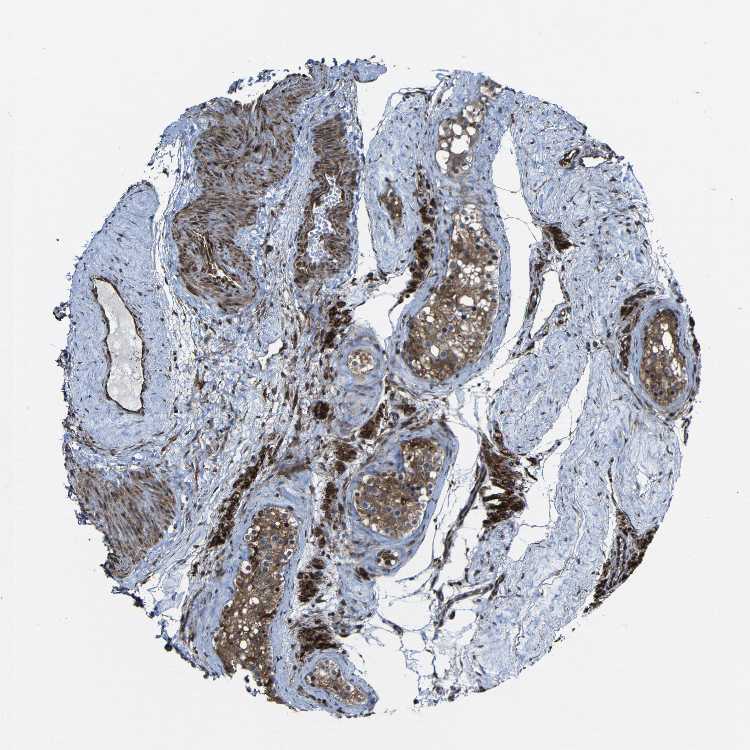

Antibody staining in the annotated cell types in the current human tissue is reported as not detected, low, medium, or high. This score is based on the staining intensity and fraction of stained cells.